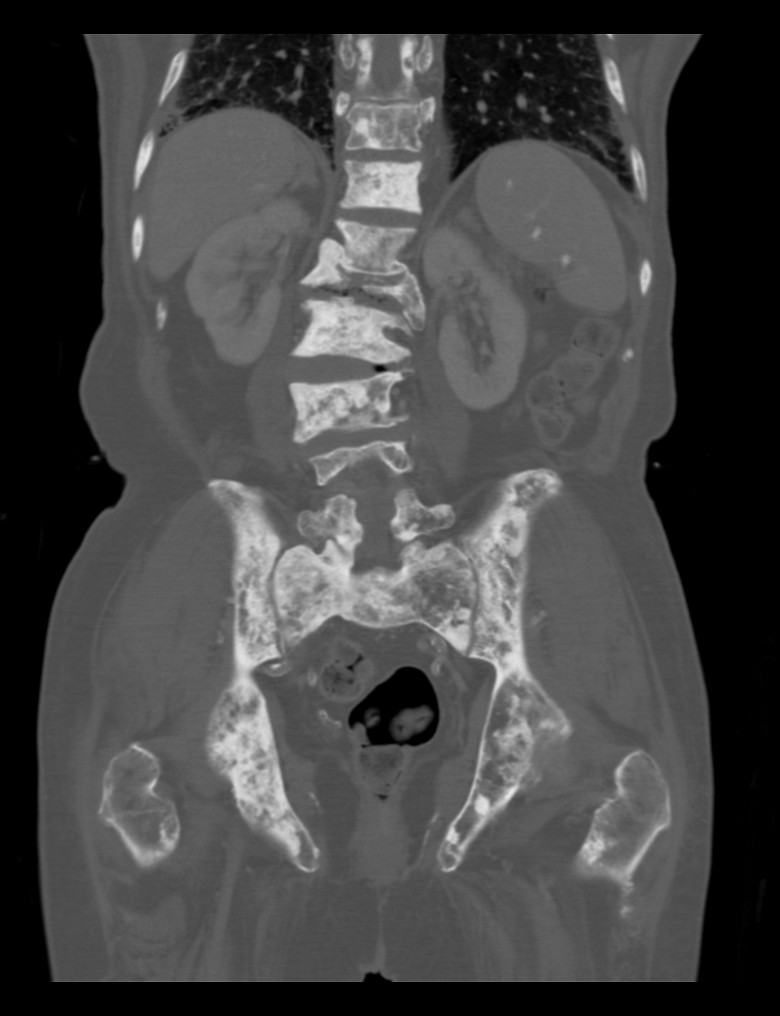

Abdomen and pelvic CT scan, coronal image in bone window

Staging CT scan of the abdomen and pelvis demonstrate diffuse sclerotic bone lesions in keeping with bone metastasis.